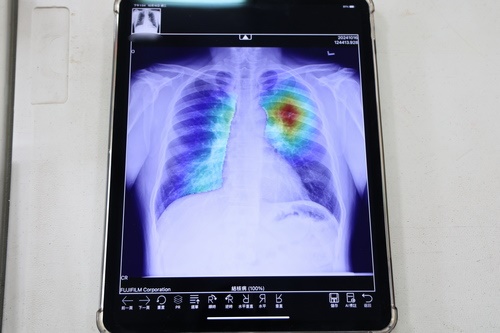

花蓮慈院在衛生福利部疾病管制署的計劃支持下,由吳彬安副院長擔任計畫主持人帶領團隊在今年導入「攜帶式X光機」,不僅收納攜帶方便,架設也很迅速,體積小可架在小型社區活動中心裡,讓鄉親就近檢查,增加他們篩檢的意願。人工智慧醫療創新發展中心(下稱AI中心)專案經理組組長王志傑表示,團隊也整合院內開發的肺結核AI模型,以及X光機,將影像結果呈現於商之器 (EBM)系統上,使用iPad便能查閱影像,並立即提供操作者肺結核篩檢的風險提示,同時,透過系統可傳送有風險影像給指定醫師遠端閱片,第一時間判斷是否留痰,免去民眾等待的空窗期。

右圖:使用iPad便能查閱影像,並立即提供操作者肺結核篩檢的風險提示,同時,透過系統可傳送有風險影像給指定醫師遠端閱片,第一時間判斷是否留痰,免去民眾等待的空窗期。